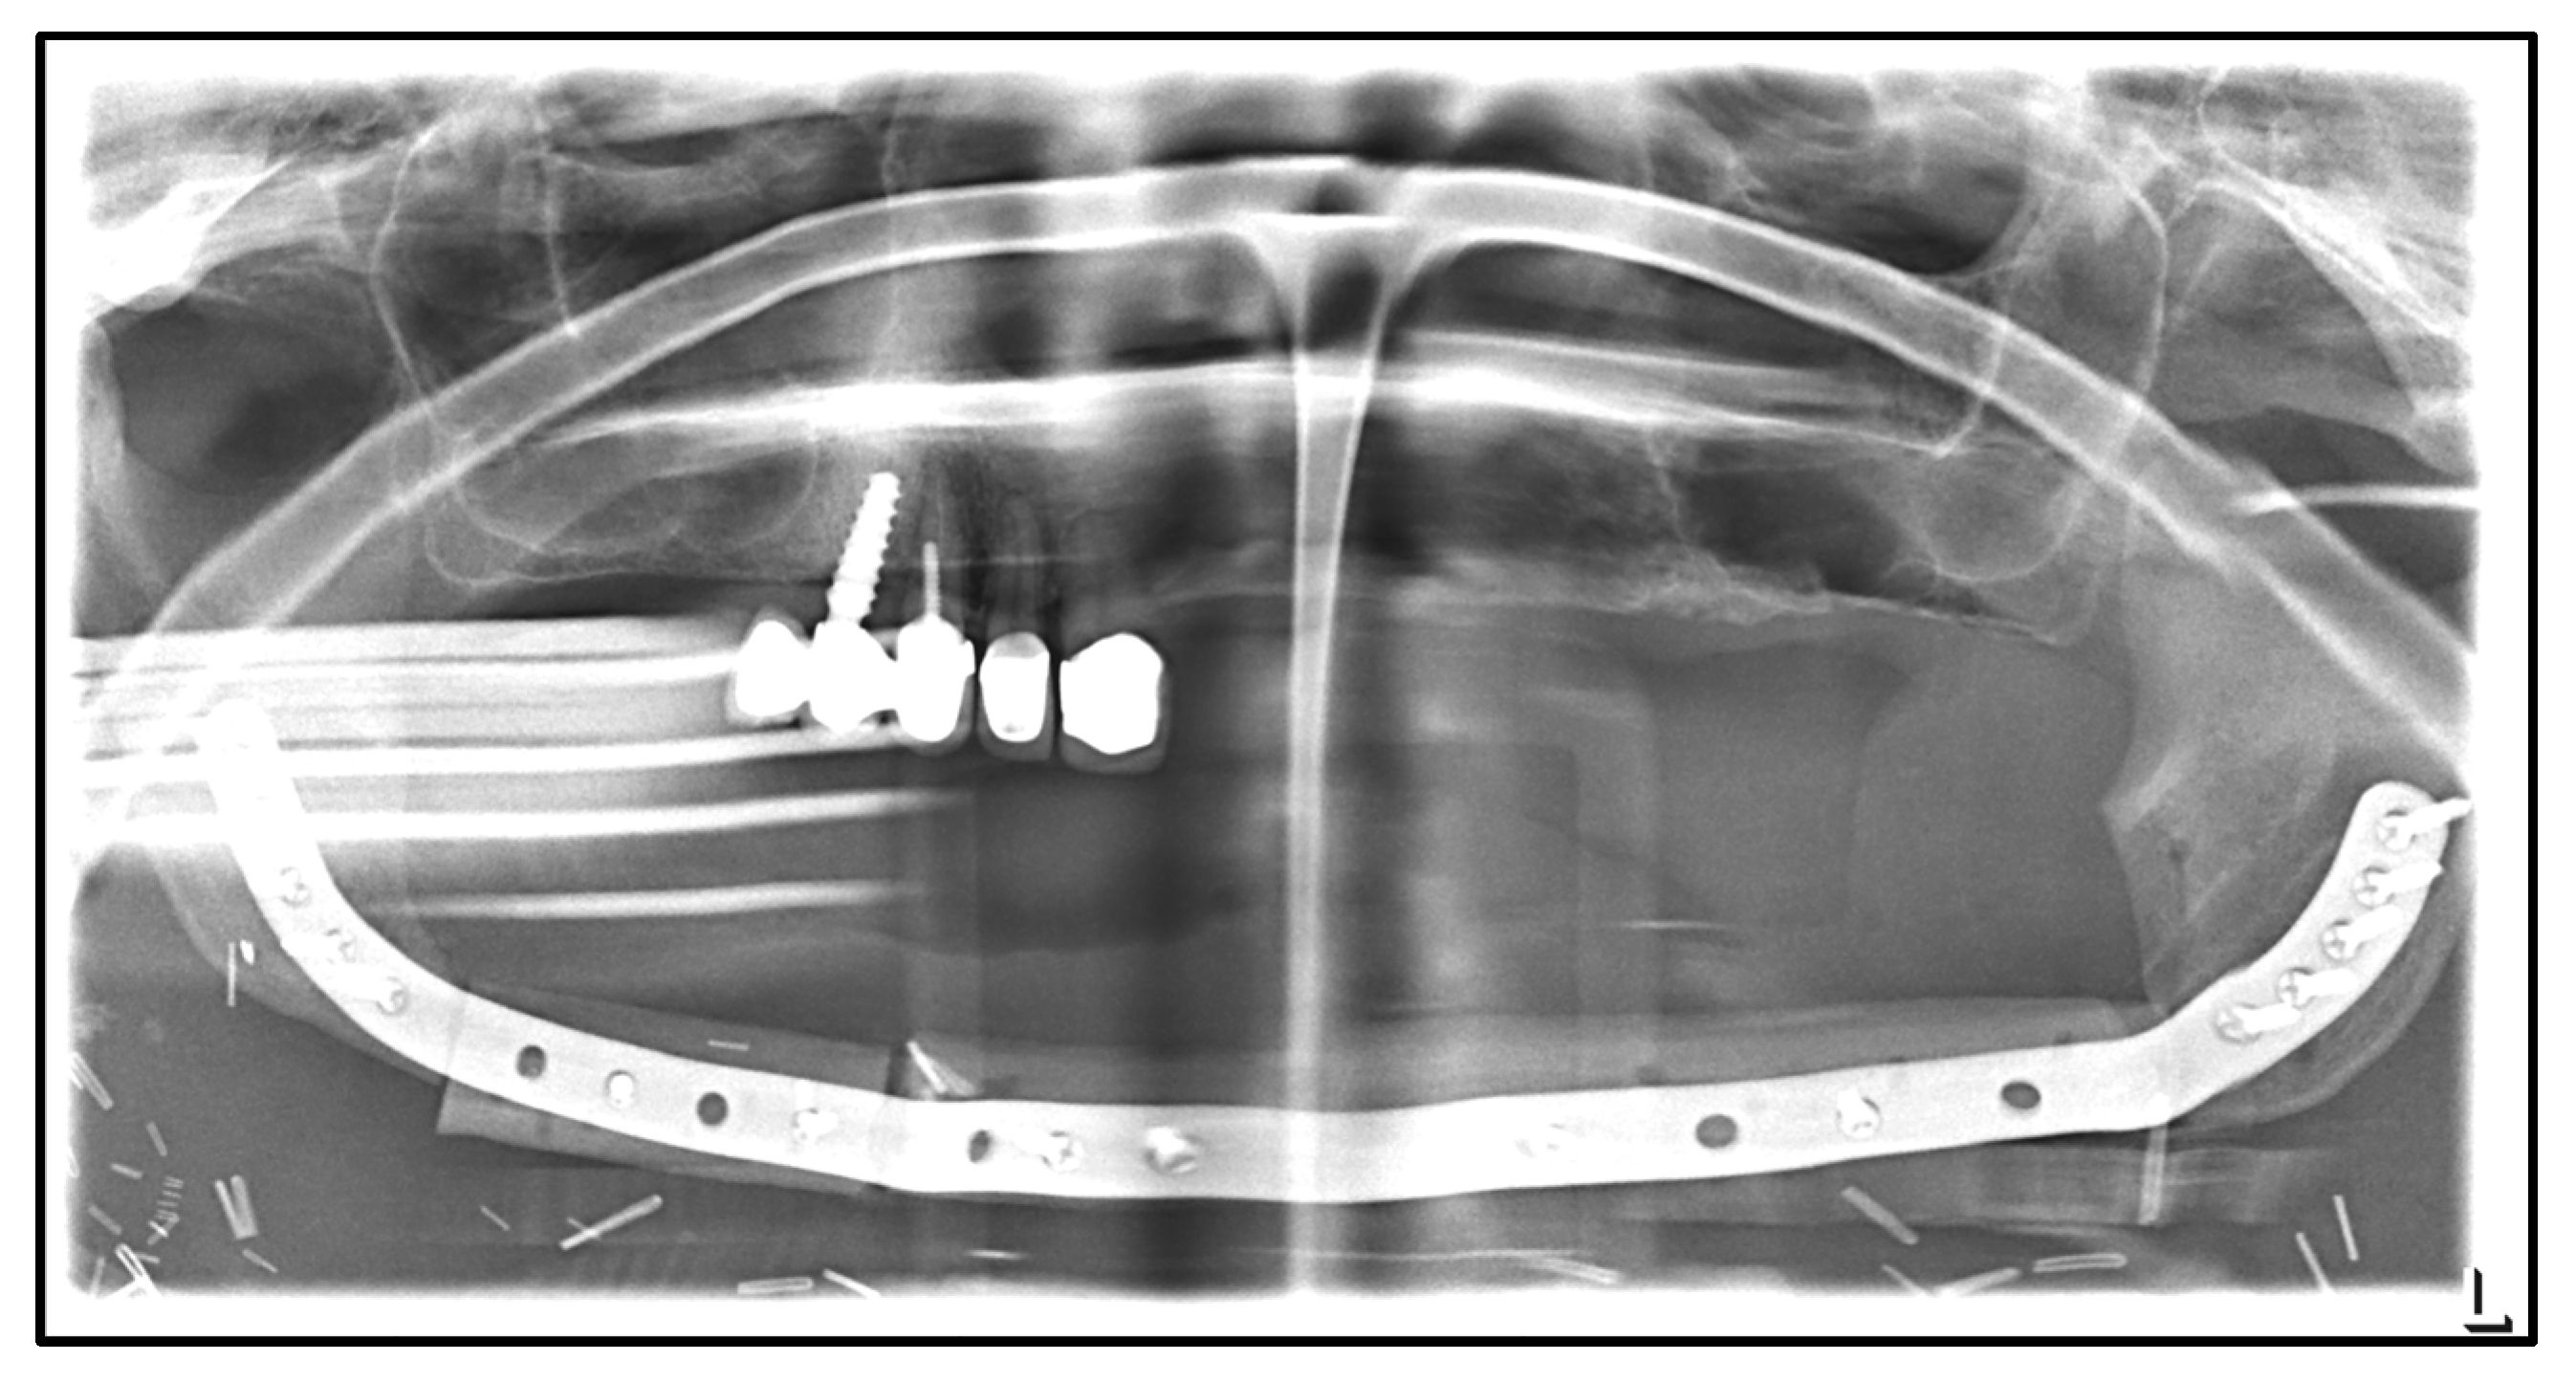

| April 2020: | Partial mandibular resection from the left to the right mandibular angle, CAD/CAM-assisted reconstruction using a free fibular graft and PSI, temporary tracheostomy. In the course: development of aspiration pneumonia treated with piperacillin and tazobactam 4.5 g for 8 days. |

| April 2021: | Placement of four dental implants in the neo-mandible for dental rehabilitation. |